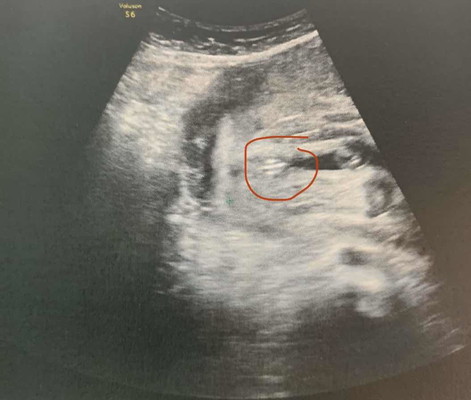

ซาวเพศลูก หญิง ชาย

อยากทราบว่าแบบนี้ผู้หญิงชัวไหมค่ะ ไม่เข้าใจขี้ตรงกลางแต่หมอบอกผู้หญิง มีสิทธิ์เป็นผู้ชายไหมค่ะ ยังไม่ได้ซื้อของกลัวไม่ตรงค่ะ ???

ผญ ค่ะ กลีบมาเชียว